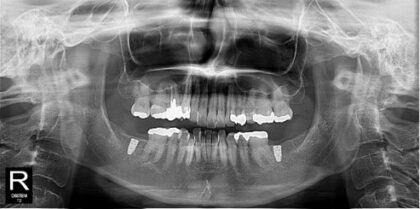

術前レントゲン

術後レントゲン

| 主訴 |

奥歯が痛い。インプラントを含めて治療を相談したい。 |

| 治療内容 |

右下6番、右上6番は歯根破折のため抜歯しインプラント治療を行う事になりました。リッジプリザベーション(抜歯後に骨が吸収するのを防ぐ処置)を行い、抜歯後約2ヶ月でインプラント埋入を行いました。右上6番は上顎洞(副鼻腔)まで3mmの厚みしかなかったため、CGF(骨再生材料)を用いてソケットリフト(副鼻腔の粘膜も持ち上げて骨の高さを作る処置)を行いました。骨結合後に二次手術(インプラントの土台をつける処置)を行い、ジルコニア製上部構造を装着しました。 |